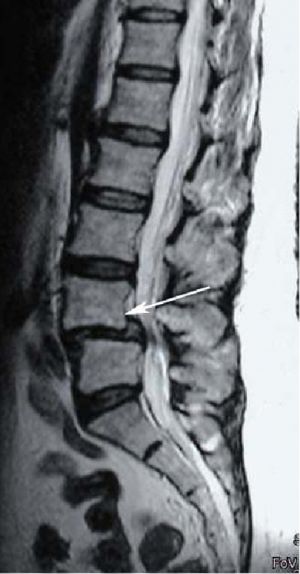

Спондилолистез

Рис. 1. МРТ поясничного отдела позвоночника. Антеролистез L4 позвонка. Стрелкой указано смещение L4 позвонка кпереди. Рис. 1. МРТ поясничного отдела позвоночника. Антеролистез L4 позвонка. Стрелкой указано смещение L4 позвонка кпереди.

Спондилолистезом или листезом (spondylolisthesis, от греч. spondylos позвонок + lysthēsis скольжение) – называется смещение одного позвонка, относительно другого нижерасположенного позвонка, обычно в передне-заднем направлении.  При смещении позвонка кзади процесс называется ретролистезом, кпереди – антелистезом. Также встречается латеральное смещение позвонков, т.е. смещение позвонка в сторону, имеющее меньшее клиническое значение. Наиболее часто поражается пояснично-крестцовый отдел позвоночника. Пациентов обычно беспокоит боль в пояснице, вызванная смещением позвонков. Компрессия нервных структур вследствие сужения позвоночного канала ведет к корешковому синдрому и вызывает боли в одной или обеих ногах. В более редких случаях встречаются нарушения тазовых функций в виде задержки или учащенного мочеиспускания с корешковыми болями, или еще реже только нарушения тазовых функций.